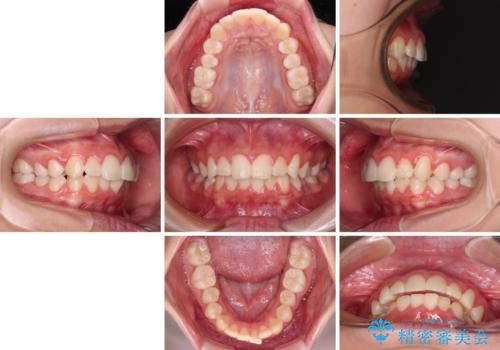

- 口元の突出感で口が閉じにくいとのことで来院された患者様です。

上下左右の第一小臼歯4本を抜歯し、ワイヤー装置での抜歯矯正を行うこととしました。

右側の咬み合わせは、上顎がやや前方位にある状態であったので、通常は補助装置を併用するのですが、高校生ということで補助装置なしで治療を行うこととしました。

口元の突出感が解消され、睡眠時の口呼吸が改善されました。